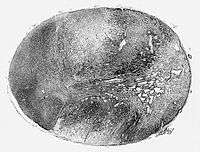

Glioblastoma arising in an astrocytoma. This spinal cord exhibits both a lightly staining microcystic astrocytoma as well as a darkly staining glioblastoma. | |